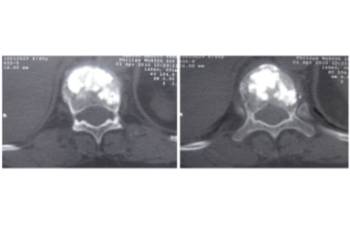

Pre- and post-operative comparison of a cemented kyphoplasty

Female, age 55, compression fracture of L2

Before 1

After 1